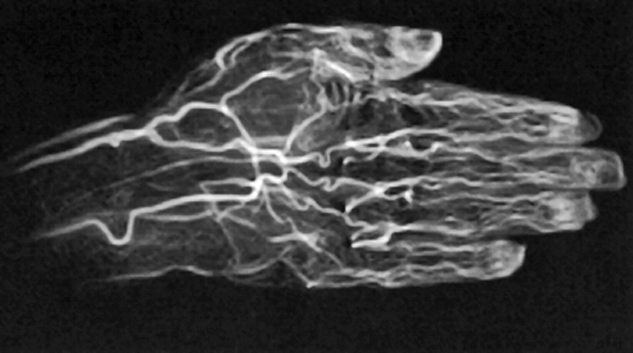

Figure 14-21:

CE TOF angiography of a hand.